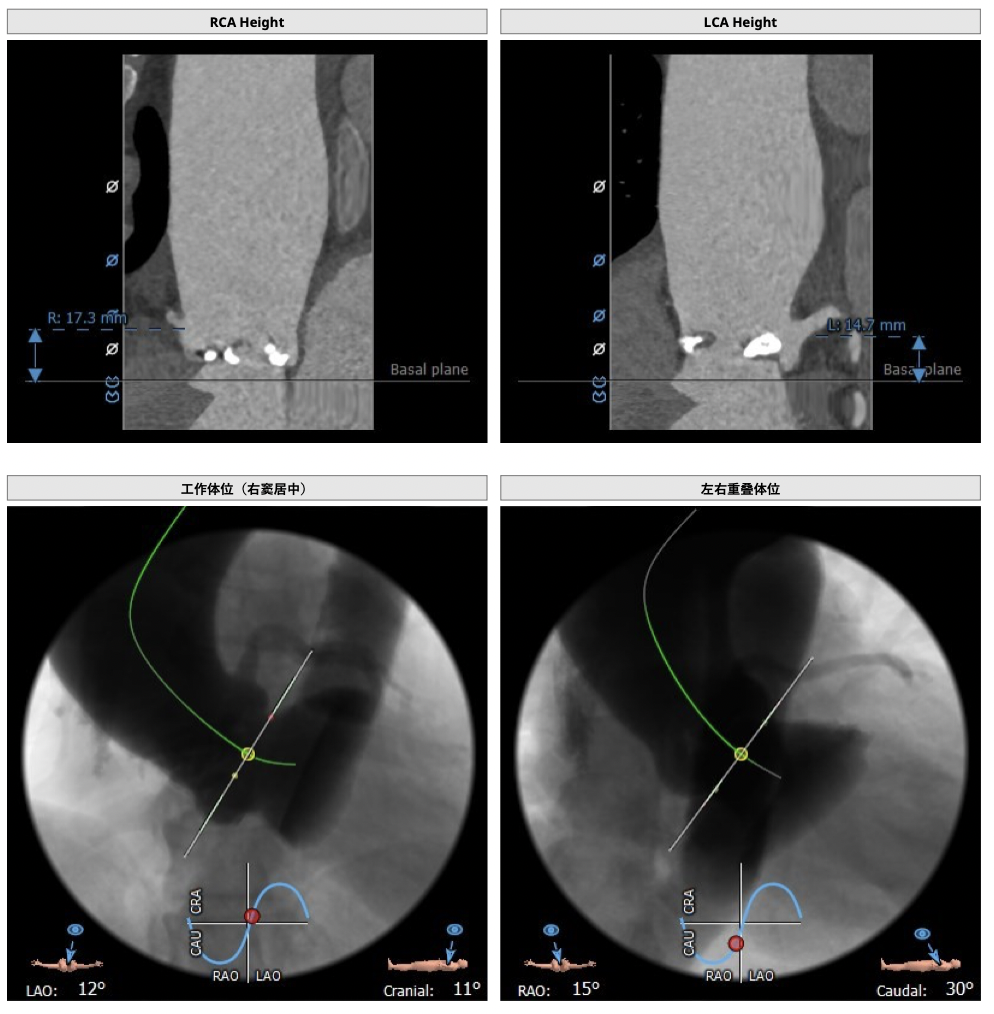

*心脏角度为60°,横位心,输送器过瓣难度增加,瓣膜植入同轴性差,瓣膜释放更易移位,增加了操作的难度;

经分析研判,拟从右侧股动脉穿刺入路,使用23mm球囊预扩,采取downsize手术策略,选用L26号的VenusA-Valve瓣膜,因患者为横位心,瓣膜释放同轴性差,容易发生移位,故采用VenusA-Plus可回收输送系统确保瓣膜的稳定释放,瓣膜释放后结合造影和超声情况,决定是否后扩。

经分析研判,拟从右侧股动脉穿刺入路,选用L26号的VenusA-Valve瓣膜,采用VenusA-Plus可回收输送系统确保瓣膜的精确释放,瓣膜释放后结合造影和超声情况,决定是否后扩。